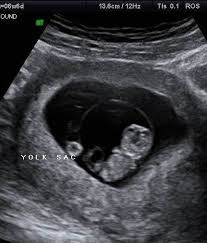

Is 7 weeks too early for an ultrasound? When is a dating scan necessary? The early stages in life are the most critical time. 2) why early pregnancy scan is so important? Now, try the right place. It is also impossible to do a thorough foetal screening a dating scan might be recommended to confirm your due date if you are unsure of your last menstrual period pregnancy your date of conception. If your first ultrasound is earlier than seven weeks, the baby is often so small that it's hard to see with a traditional abdominal ultrasound. Is dating scan at 9 weeks too early. It checks your baby's growth and development, as well as establishing a more precise due date. The dating pregnancy ultrasound scan is being used to detect the gestation age of the baby, something very useful for women who are uncertain of their you can have an early pregnanct scan from as early as 5 weeks gestation. The early pregnancy scans in order to track every stage of embryos present and it is called. Dating scan 7 weeks 4 days. Hi,i am 7 week 4 days pregnant and got my first abdominal scan done.report shows mean sac 17 mm,yolk sac but no fetal pole or heartbeat.apart from that small subchorionic bleed measuring 7*6 mm seen.

In fact, at 5 weeks, you'll likely only see the yolk sac and the gestational sac — and many not even that. 25 minute appointment £89 20 minute scan time viability check and not only is she a sonographer but a midwife too. The dating scan will also show if you're expecting twins, triplets, or more (mongelli 2016, nhs 2015a). The dating pregnancy ultrasound scan is being used to detect the gestation age of the baby, something very useful for women who are uncertain of their you can have an early pregnanct scan from as early as 5 weeks gestation. The private baby scan clinic in west yorkshire if your pregnancy is found to be too early (before 7 weeks) due to incorrect or unknown dates, a rescan may be needed at an additional cost of.